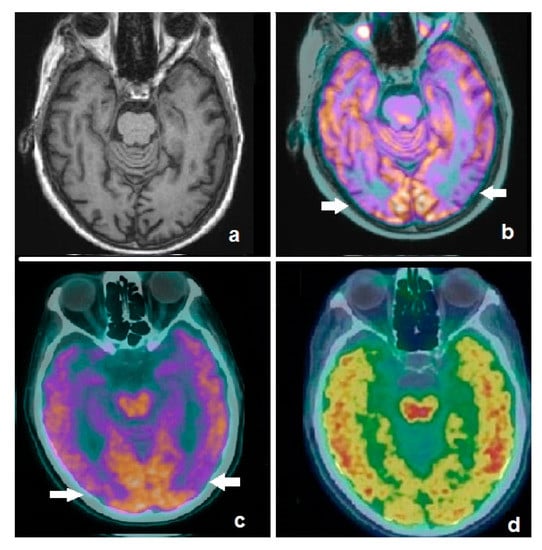

4.1. Dopamine Transporter (DAT) Imaging in SNCApathies

4.3. FDG-PET Imaging in SNCApathies

5.1. FDG-PET Imaging in Atypical Parkinsonian Syndromes